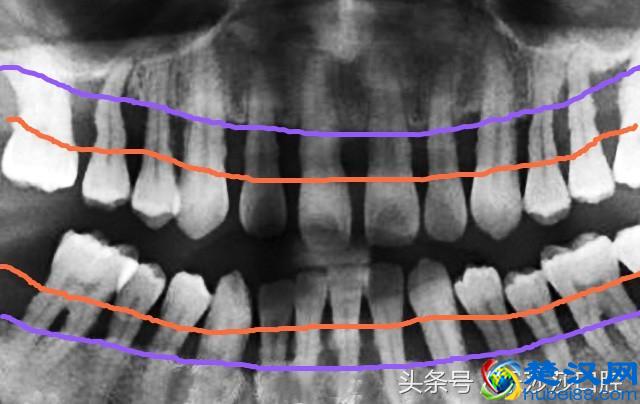

如上图所示,橙色线为正常牙龈高度,当患有牙周炎,会累及「牙槽骨」,导致牙槽骨慢慢流失(紫色线),这时牙齿就失去了「支撑的土壤」,开始松动甚至脱落。坦白来讲,牙周炎发展到这种程度,很多时候医生也「束手无策」!为了保留更多的牙槽骨,医生会不得不拔掉严重松动的牙。